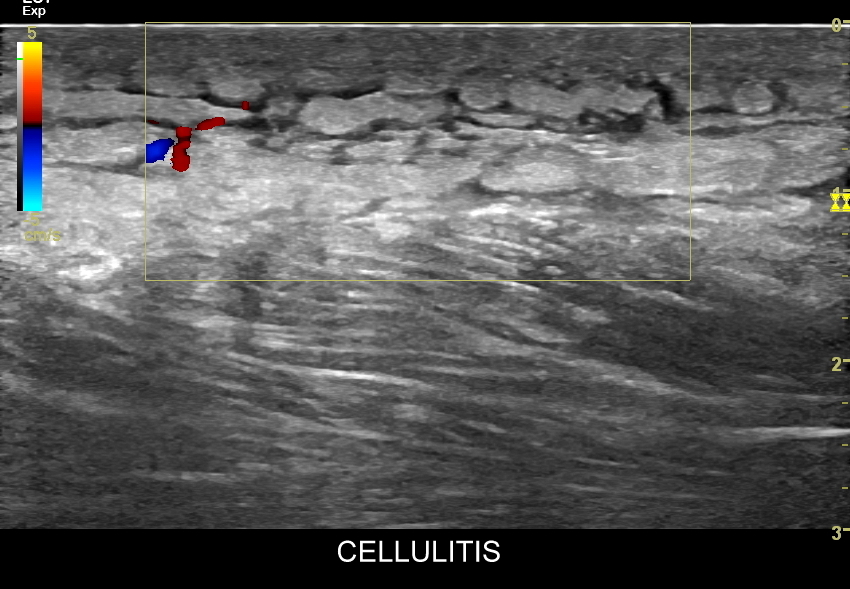

Podsumowując, w stanie fizjologicznym każda warstwa posiada swoją własną, wewnętrzną echostrukturę oraz jest ostro oddzielona od warstw sąsiadujących. W przypadku pojawienia się rozlanej patologii w powłokach lub ich konkretnych warstwach dochodzi do pojawienia się niespecyficznego, ale bardzo czułego objawu zatarcia (ang. cutaneous blurring sign), który polega na podwyższeniu echogeniczności tkanki, zatarciu wewnętrznej struktury danej warstwy oraz zatarciu granic pomiędzy poszczególnymi warstwami powłok.

Objaw zatarcia występuje w różnorodnych schorzeniach, głównie rozlanych, lokalizujących się w skórze i powłokach, w tym w obrzękach żylnych i limfatycznych; w zapaleniach infekcyjnych, odczynowych, metabolicznych, autoimmunologicznych; w urazach mechanicznych, fizycznych i chemicznych; w krwawieniach i skazach krwotocznych; w dermatozach. Okazjonalnie stwierdzany jest w zmianach ogniskowych, gdy mają one zatarte granice i jednocześnie zacierają fizjologiczną strukturę tkanki podskórnej. Przykłady patologii zobaczyć można w załączonych do artykułu zdjęciach.